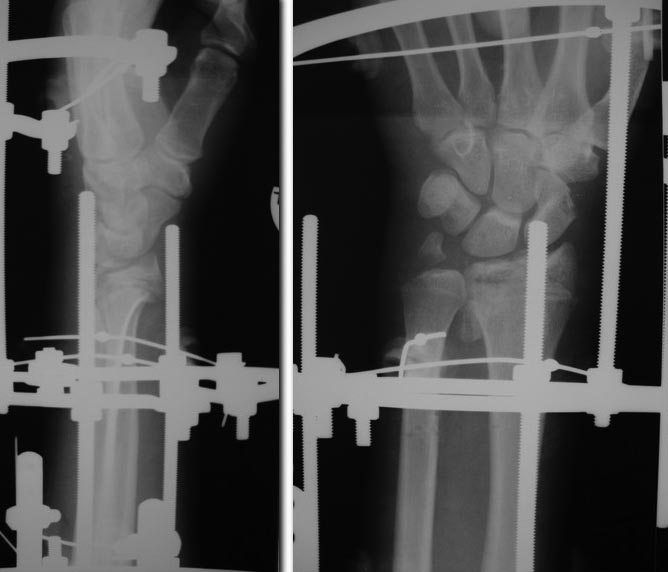

Доброго времени суток, глубокоуважаемые коллеги! Прошу помощи по лечению суставного перелома дистального метаэпифиза лучевой кости Пациент 22 лет. Травма в результате ДТП 14.11.13. Диагноз: Сочетанная травма. Тупая травма грудной клетки. Закрытый перелом 2, 3, 4 рёбер слева, 4, 5 справа. Ушиб лёгких. Закрытый оскольчатый перелом дистального метаэпифиза левой лучевой кости со смещением отломков, вывихом головки локтевой кости, нейропраксией срединного и локтевого нервов. Ушибленная рана головы. Первично обращался в другое больничное учреждение, где произведено ПХО,закрытая репозиция. От госпитализации отказался. Через 2 дня обратился за помощью по месту жительства. Госпитализирован. Левое предплечье резко отёчно. Выявлена клиника нейропатии срединного и локтевого нервов с чувствительными расстройствами. Произведена повторная закрытая репозиция, которая не увенчалась успехом.Наложен аппарат внешней фиксации. Подвывих кисти устранён. Вывих локтевой кости вправлен. Клиника нейропатии локтевого нерва купирована. На настоящий момент сохраняется гипостезия 1п левой кисти, отёк купируется.Ввиду молодого возраста пациента и оскольчатого характера перелома планируем вторым этапом произвести погружной остеосинтез. Прошу помощи с планированием остеосинтеза. Удастся ли стабилизировать перелом из ладонного доступа, или необходим и тыльный? Каким имплантатам отдать предпочтение?

снимки в аппарате

Похоже в аппарате достигнуто неплохое стояние. Может спицей с напайкой притянуть ладонный фрагмент.